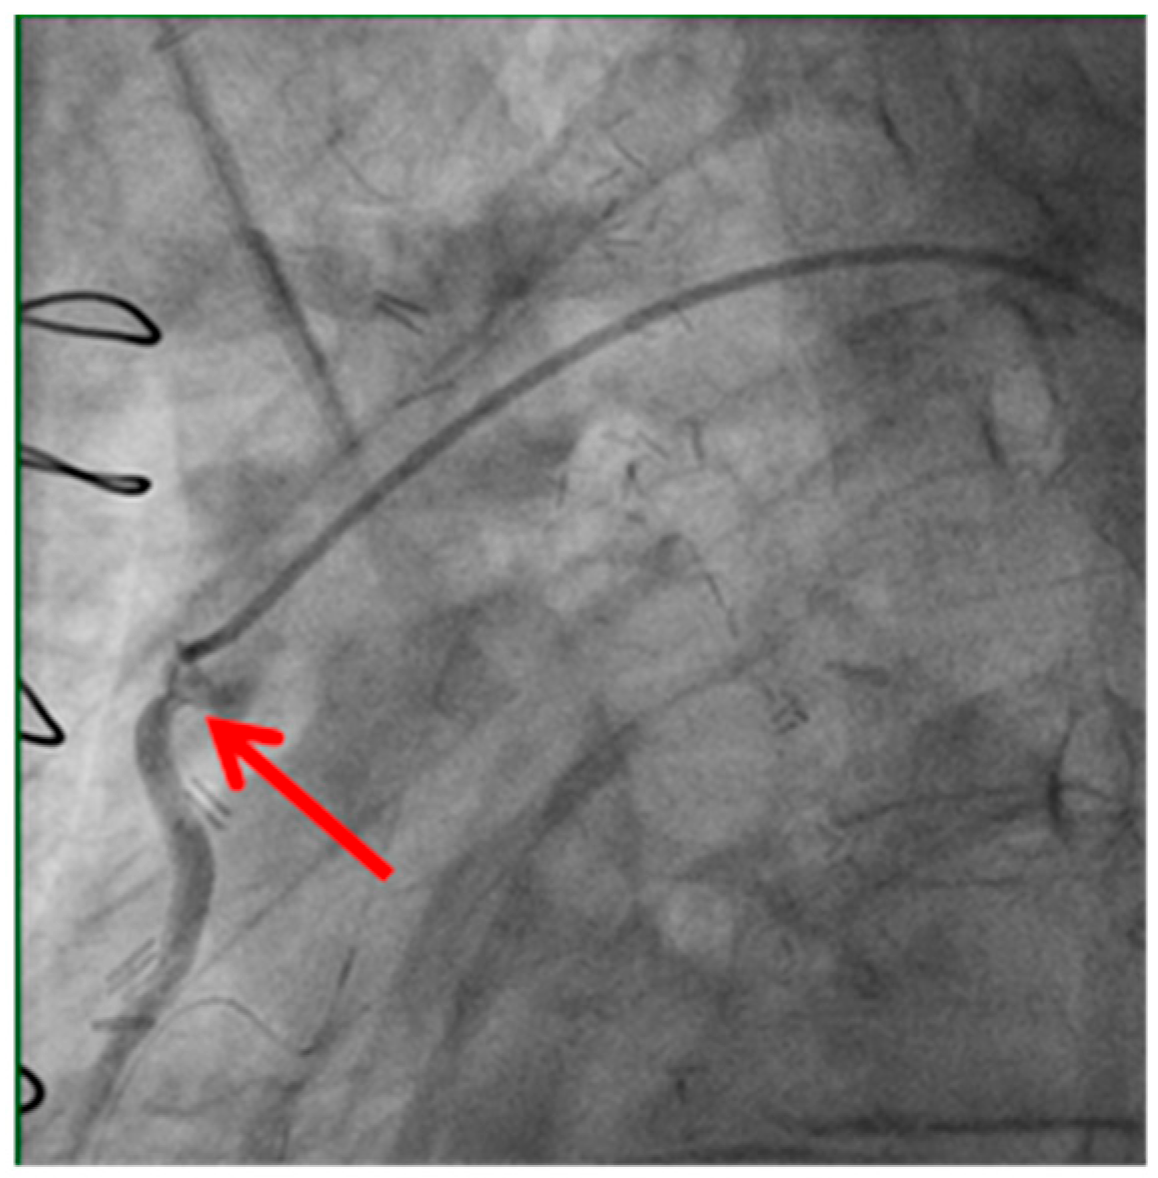

Technical issues remain a principal cause of PMI, with early graft thrombosis or occlusion being leading indications for uCAG (Figure 1, Figure 2, Figure 3 and Figure 4 illustrate typical technical causes, including proximal anastomotic stenosis, kinking, distal anastomotic stenosis, and misplaced anastomoses). Notable contributors include anastomotic stenosis, kinking, overstretching of grafts, and temporary graft spasm [13,21]. Prueßer et al. demonstrated that 30% of PMI cases detected via CAG were graft-related failures [13]. In this context, uCAG often reveals technical failures immediately post-surgery, providing the advantage of guiding targeted percutaneous coronary intervention or revascularization. Graft spasm, which can be relieved by nitrates, may also lead to acute ischemia. It refers to the temporary constriction of the bypass graft, reducing blood flow to the myocardium. This condition can be caused by various factors, including surgical trauma, inflammation, or the release of vasoactive substances [21].

Example of bypass graft kinking (shown by the red arrow) detected on angiography. Kinking may compromise graft patency and myocardial perfusion, highlighting the importance of meticulous surgical technique and intraoperative assessment.

Figure 2. Kinking of the bypass graft.